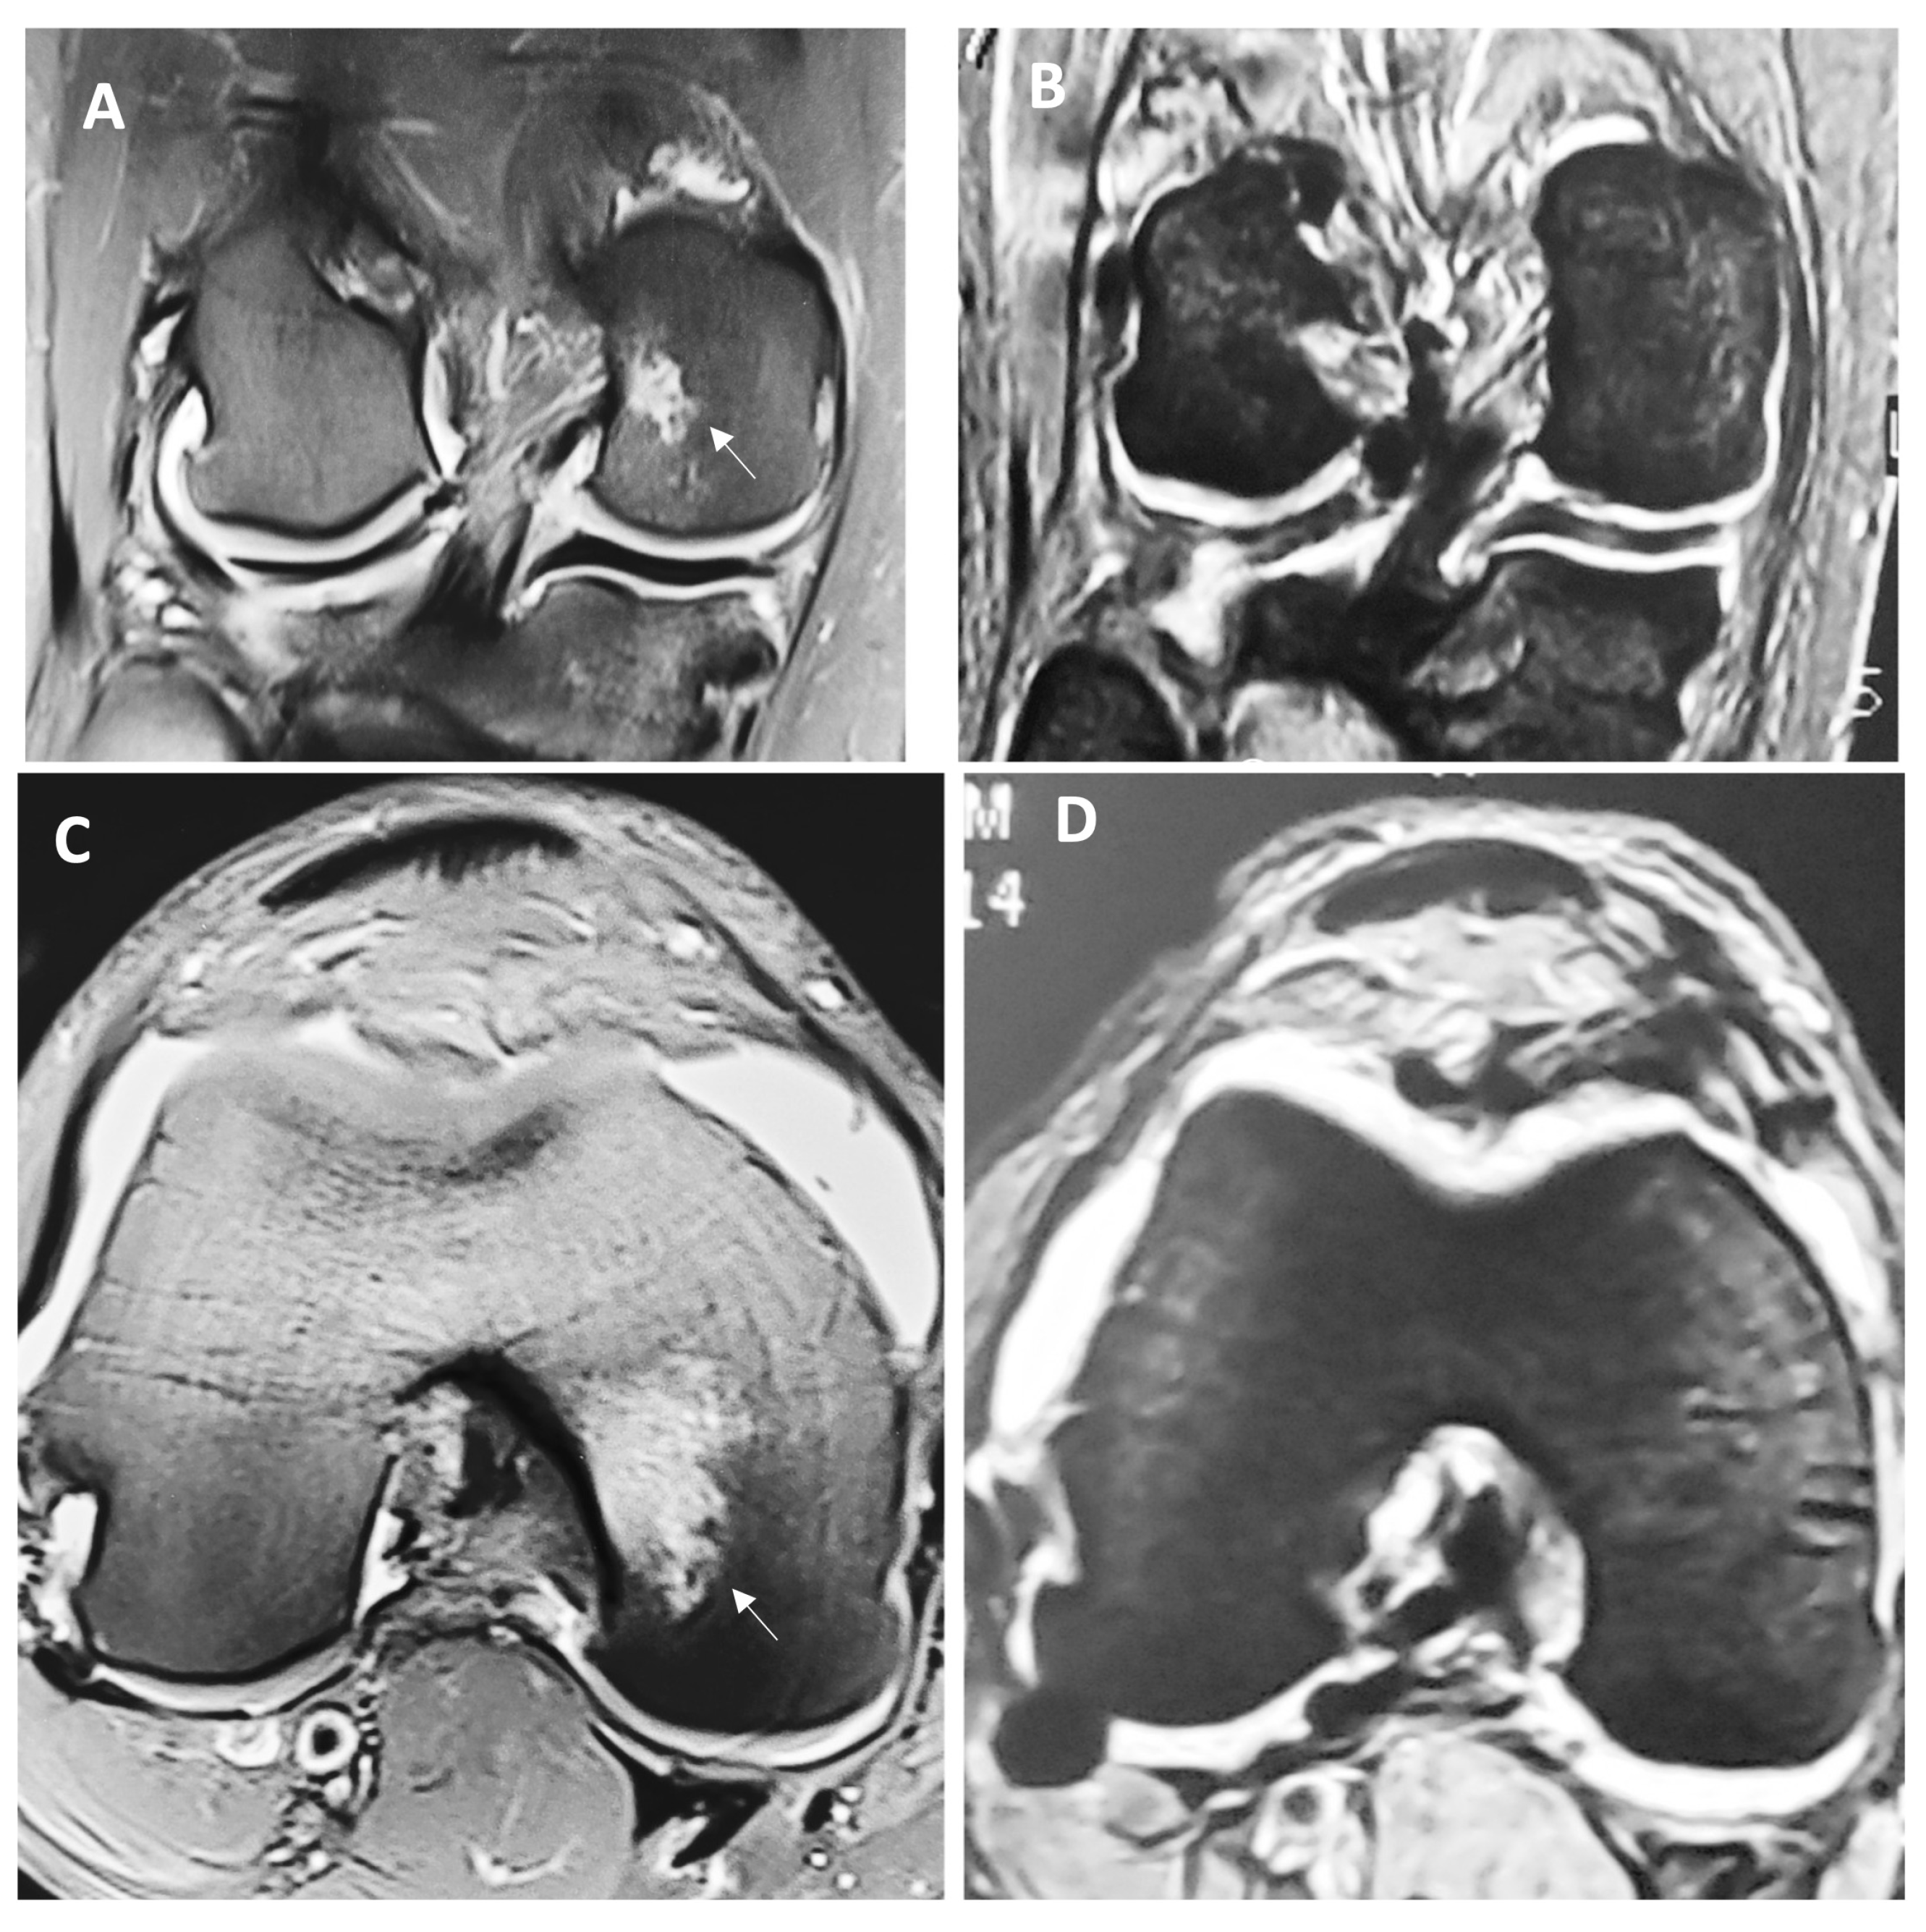

Figure 1 depicts macroscopic changes observed at 6 months in the MRI. Then, 12 months after the surgery, there was a continued improvement for both groups, but this difference was markedly important for individuals in the HA 3-D scaffold group, since all patients from this group were found to have a Henderson scale score of 1, while the group treated with microfractures still had almost half of the individuals (47.6%) with a score of 2 (p = 0.0048). This means that all patients treated with the HA 3-D scaffold returned to a radiographic image that represents a knee with an absence of fluid and edema in the joint. Conversely, in the microfractures group, this was not achieved by any patient. Table 2 represents these comparisons between groups.

Figure 1.

Representative MRI view of the full-thickness cartilage defect and adjacent tissue before (A) and (C) and 6 months after the surgery (B) and (D) in a patient treated with HA 3-D scaffold. Letter (A) represents the anteroposterior view of the knee, while letter (C) demonstrates the coronal view; both are showing cartilage damage with ICRS grade IV in the medial femoral condyle (arrow), with effusion and evident subchondral edema (Henderson score of 4). Letters (B) and (D) represent the same respective views 6 months after the intervention, where the lesion has visibly disappeared and reparative tissue is layering above; additionally, effusions and edema are absent (Henderson score of 1).